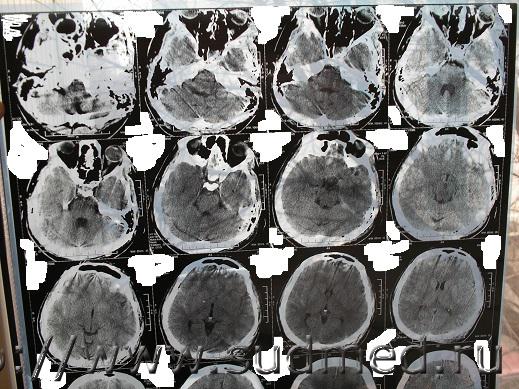

Нужно знать, что видно на данных снимках КТ. Спорная экспертиза. Делали по копии мед. карты и по этим снимкам. Снимки на руках у потерпевшего, еле достали. Исчез рентген потерпевшего из приемного отделения, осталась только запись в карте. Повреждений свода черепа не обнаружено. Диагноз в обвинении - Комплексный перелом свода и основания черепа, отоликворея слеа, УГМ средней тяжести, субарахноидальное кровоизлияние, пневмоцефалия, алкогольное опьянение, ушибленная рана на затылке. Потерпевший выписан из больницы на 18й день, более нигде не наблюдался. Говорит лечится в частном порядке. Мнение эксперта-рентгенолога - перелом клиновидной кости давностью не более 6-8 недель. А снимки сделаны в первые сутки. Есть еще пара снимков, но такого же качества и, как написано в экспертизе дополнительной информации не содержат. Очень нужно знать, что на снимках, независимое мнение. Есть еще снимок МРТ через три месяца. Информацию на дисках не предоставили.

Проконсультируйтесь с опытным рентгенологом, специалистом по КТ. Лучше - с двумя-тремя. Это придется сделать очно, т.к. информация существенно теряется: а) при перефотографировании пленок КТ, б) при пересылке через интернет этих фотографий. Полагаю, что приватным образом такую консультацию можно получить у любого подобного специалиста. Получить какое-то письменное заключение возможно при оформлении договорных отношений на кафедре рентгенологии мед.ВУЗа, в мед.центре, профилирующемся на КТ диагностике и т.д. Лучше представить ВСЕ снимки КТ (тогда более достоверно и аргументированно можно судить о динамике изменений, о давности травмы), все КТ на цифровом носителе (можно будет построить 3D-реформацию изображения, т.е. более детально определить распространение перелома).